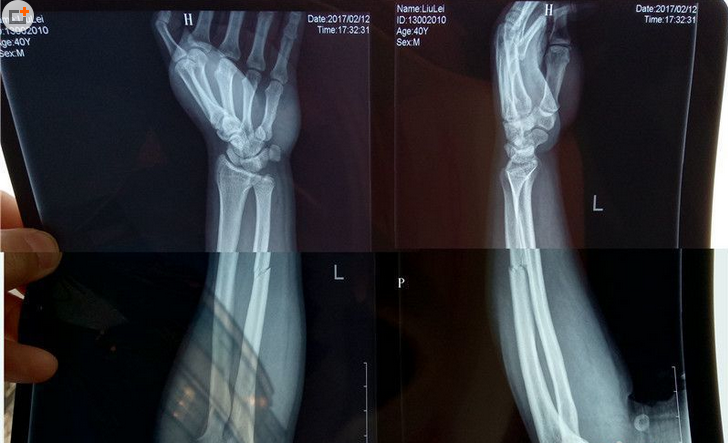

14日,刘先生出示在咸阳市第一人民医院就诊的诊断证明及X光片。诊断证明显现左臂尺骨骨折。X光片显示刘先生左臂上的骨头已经明显断成两截。